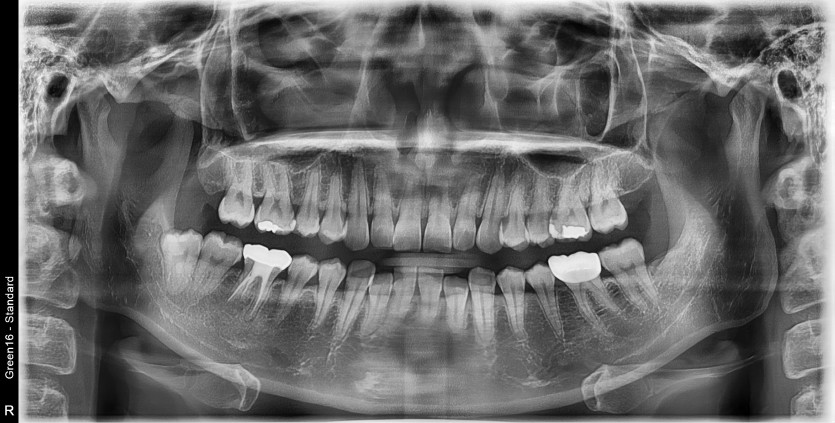

#48 사랑니 발치

구강외과 전문의가 당일 발치했습니다.